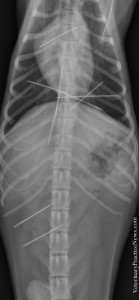

而每年都會舉辦的They Ate What X光大賽,至今已舉辦了9年,2014年的冠軍是一隻吞下超過30塊石頭的寵物蛙,第二名是吞下烤肉串的波音獵犬,第三名則是住在波特蘭的大丹,X光片發現有大量異物,手術後取出居然是43隻加半隻襪子而一名成名,只是主人一下子不見了43隻襪子,難道不曾懷疑是狗兒闖的禍嗎?看到照片中那排成一整排的襪子,真的要它們被拉出來實在太困難了啦~好在經過手術隔天,大丹順利返家休息,開始下一個奇幻冒險旅程?